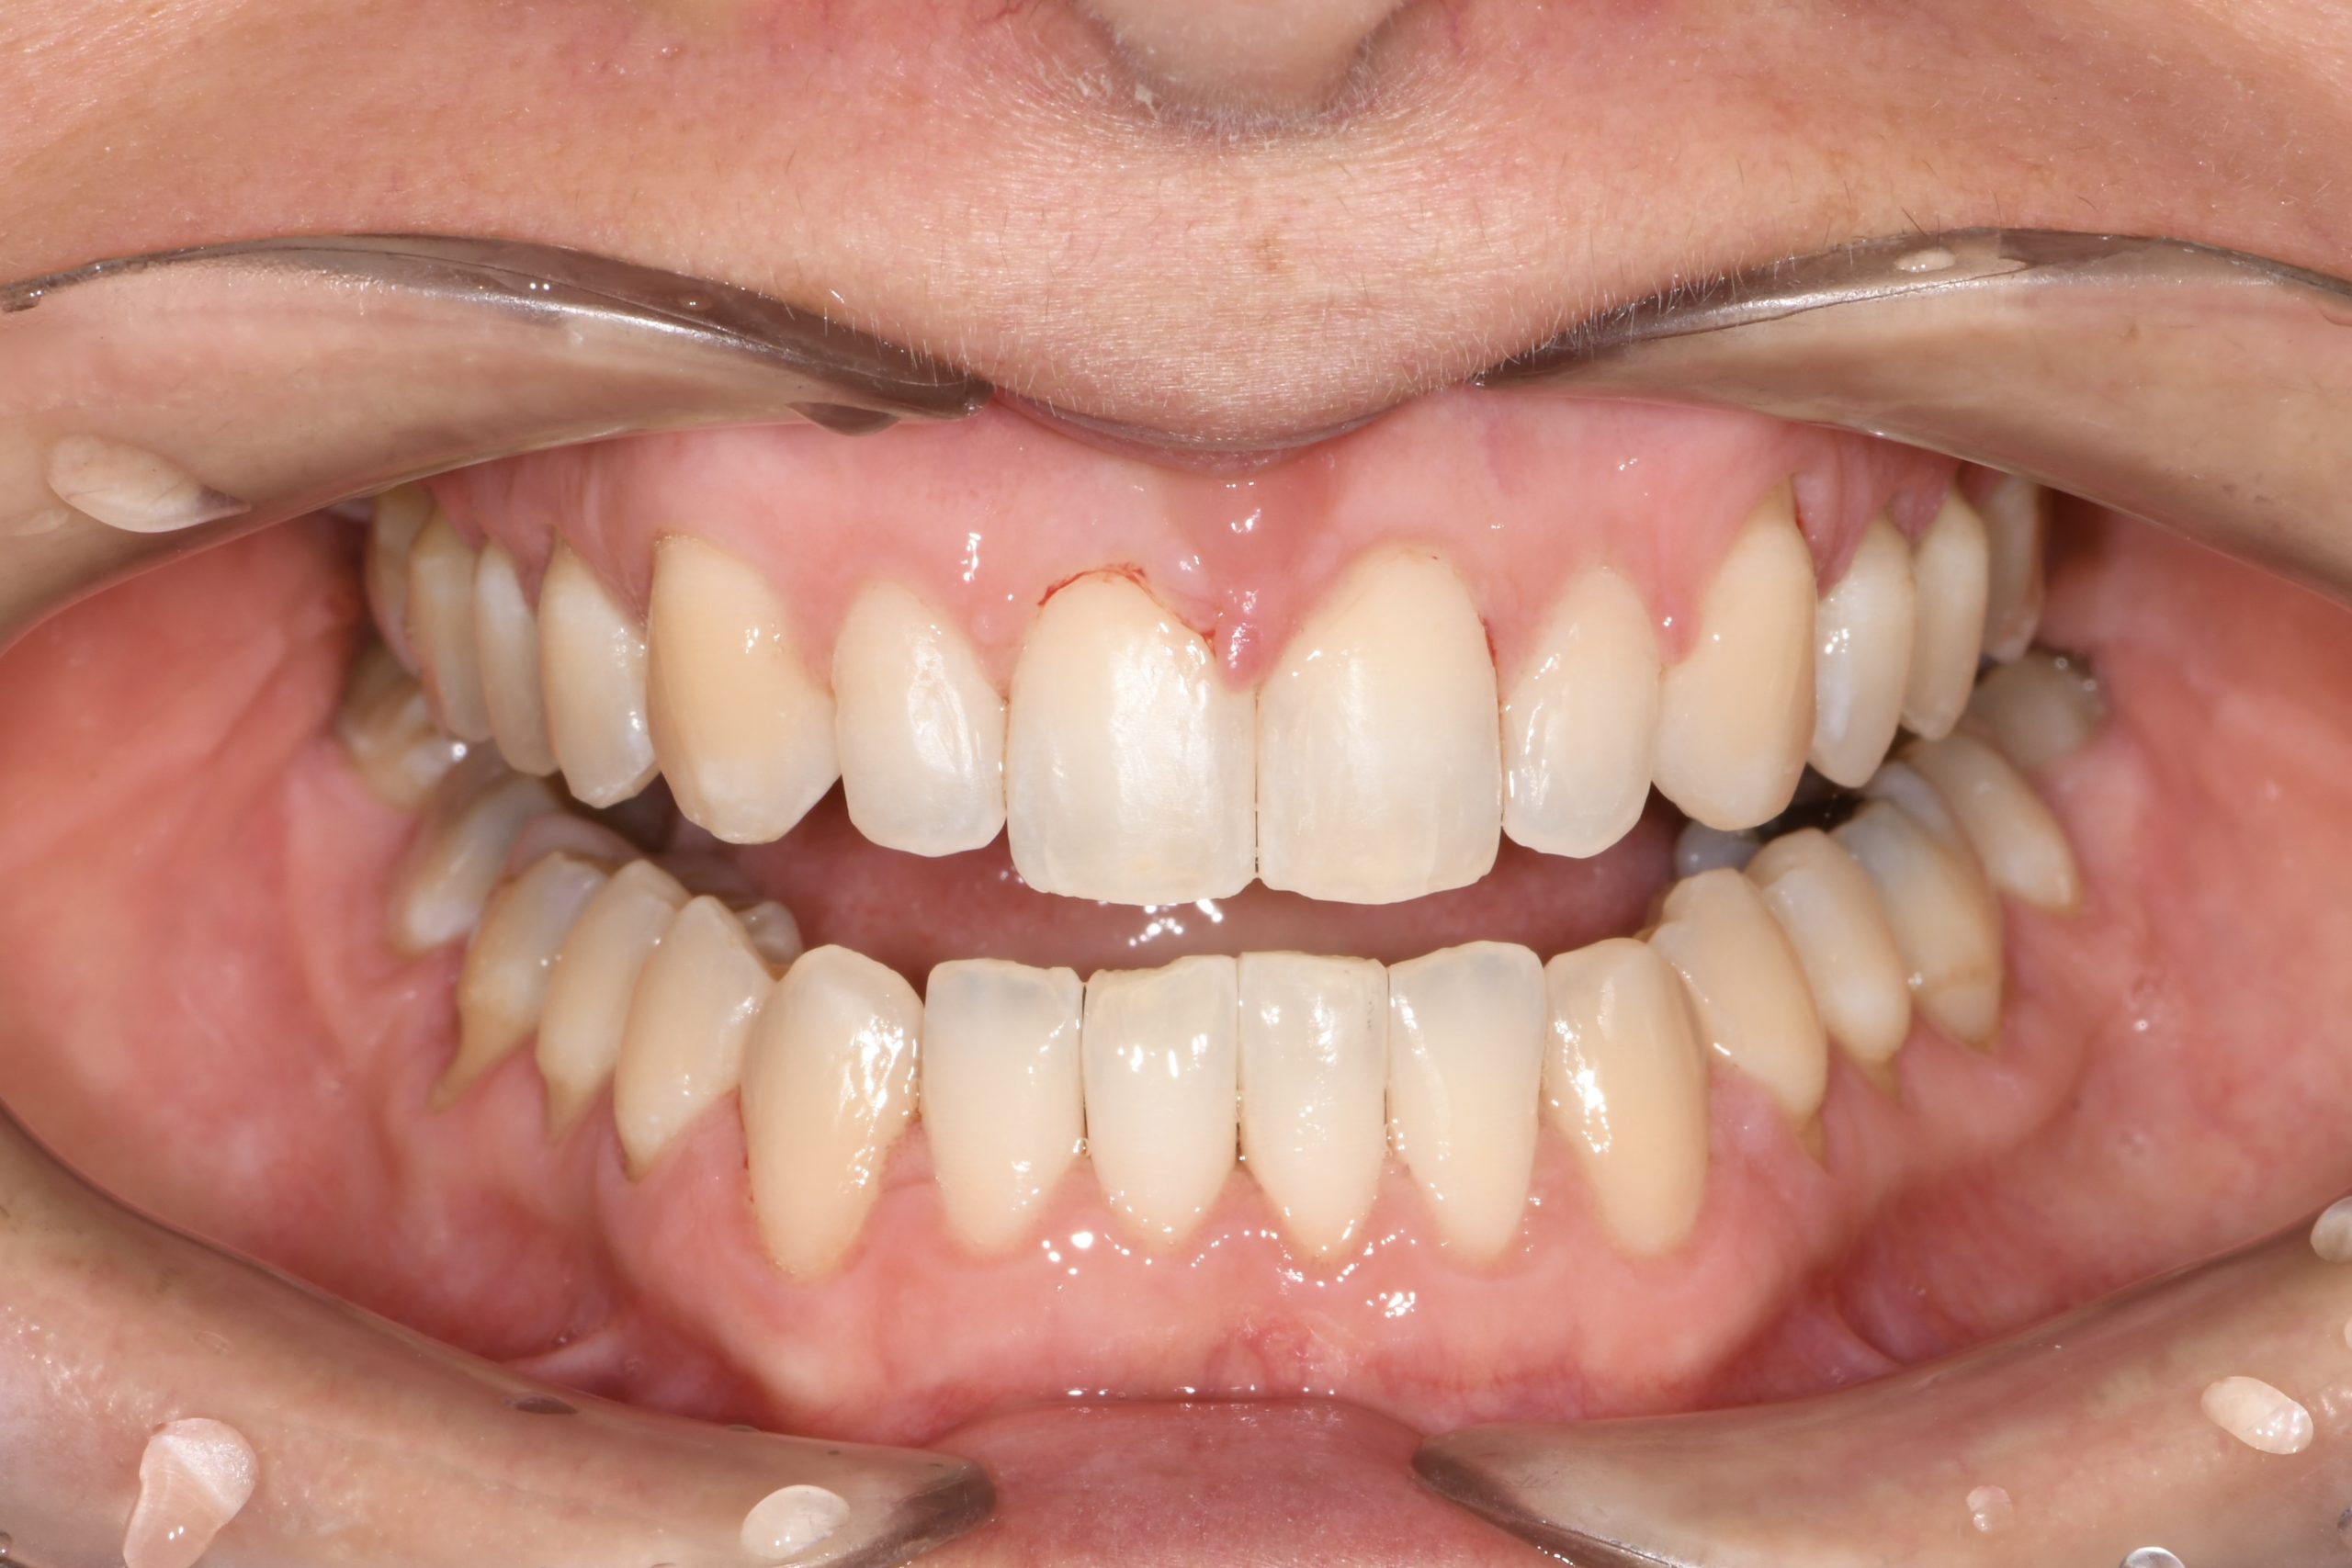

Az elmúlt évekből rengeteg szakmai referenciát tudnánk bemutatni, amelyek különböző fogszabályozási problémákat oldottak meg. Válogatva a több száz esetből, ezen az oldalon olyan képeket, információkat igyekeztünk bemutatni, amelyeknek a segítségével a jövőbeni pácienseinknek azt tudjuk üzenni: A Te fogsorod is lehet gyönyörű!

(Képeket a Pácienseink külön írásos beleegyezésével mutatjuk be!)